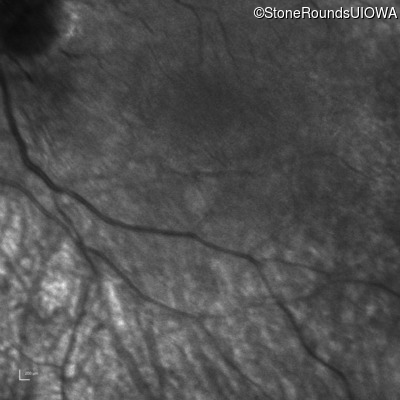

Infrared Fundus Photograph - Right -

No Light Perception

Exemplar

Infrared Fundus Photograph - Left -

Light Perception